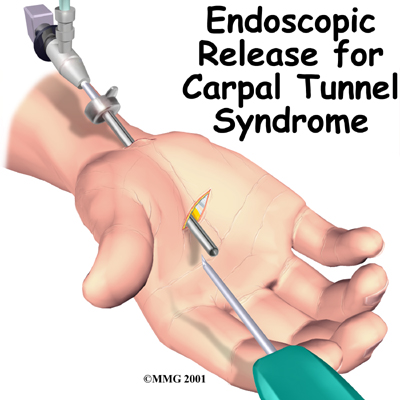

Endoscopic Carpal Tunnel Release Patient Guide

Carpal Tunnel Syndrome (CTS) is a condition affecting the wrist and hand. While the most common surgical procedure for carpal tunnel syndrome is still the open-incision technique, some surgeons are using a new procedure, called endoscopic carpal tunnel release.This procedure is done using an endoscope (a small, fiber-optic TV camera) to look into the carpal tunnel through a small incision just below the wrist. Using the camera allows the surgeon to release the problematic tissue without disturbi...